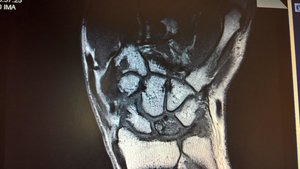

die durchblutung des knochens wird einfach eingestellt, dann stirbt er ab und beginnt zu frakturieren.

das ist bei mir bereits der fall... danach zerbröselt der knochen komplett und wenn es nicht gleich operiert wird, kommt es rasch zu einem handgelenkkollaps und das gelenk muss komplett versteift werden. das möchte ich vermeiden und wenigstens eine restbeweglichkeit behalten(in der hoffnung, viele bewegungen umlernen zu können)